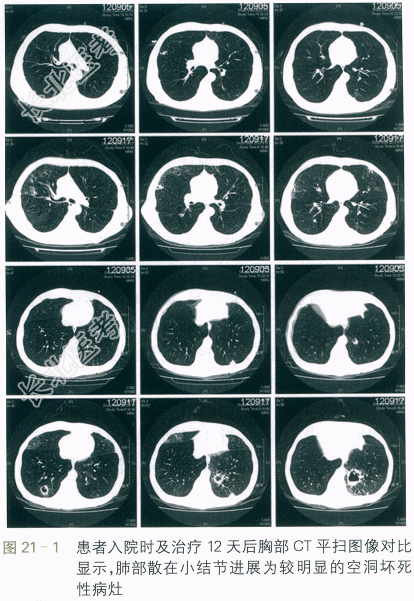

62mmHg。cTnT在正常范围,BNP670ng/L。入院当天胸部CT(见图21-1)提示双肺肺气肿表现,两肺少许散在结节样病灶,考虑炎性病灶可能大。心超提示肺动脉收缩压38mmHg,其余无明显异常。